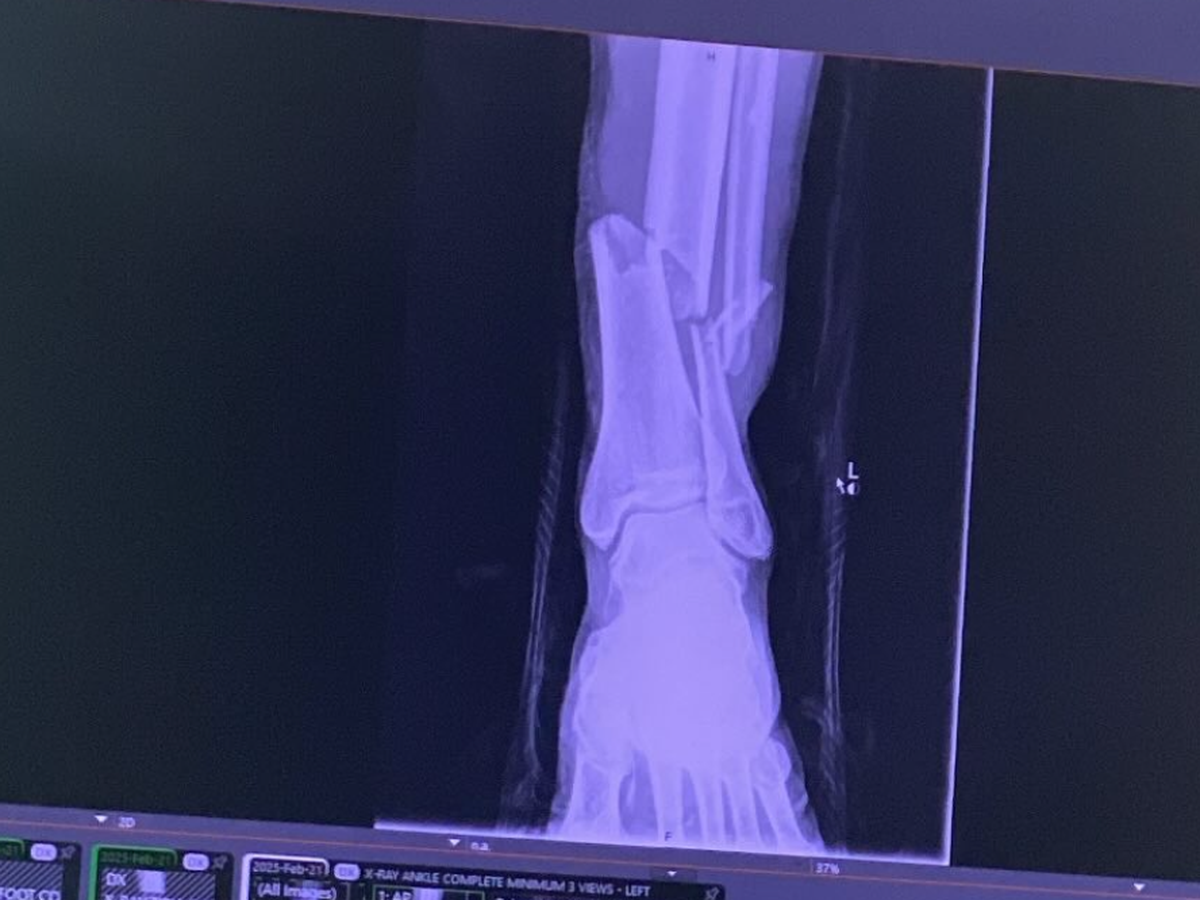

This is a fundraiser to help Michael Deon with his medical bills from our recent fight on Feb 21st. He suffered a complete break of his left leg and he underwent surgery the following day. He now has a Titanium Rod in his shin. We’re wishing him a speed recovery and donations would be greatly appreciated